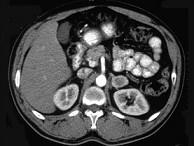

问题 女,34岁,无意中发现血压升高4个月就诊,行CT检查,如图所示,下列说法正确的是()

选项 A.CT示左侧肾上腺区可见一等密度块影,边界清楚 B.增强扫描,该病灶周边明显强化,中心处强化不明显 C.考虑为左肾上腺腺瘤 D.考虑为左肾上腺嗜铬细胞瘤 E.考虑为左肾上腺转移瘤

答案 ABD